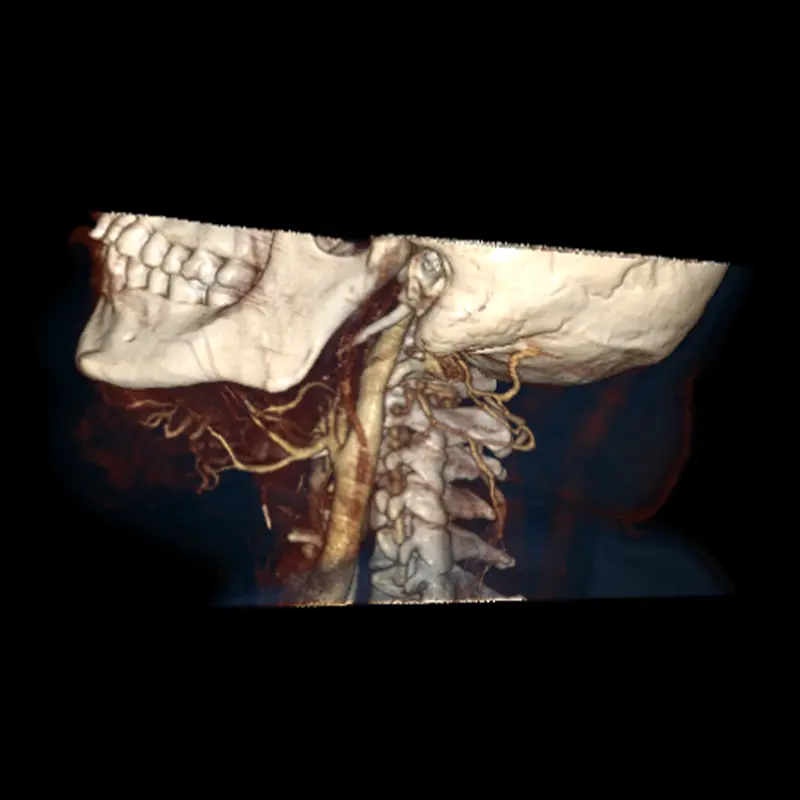

Malformaciones vasculares hemangionas

El diagnóstico y el tratamiento de las malformaciones arteriovenosas requieren un amplio conocimiento de esta rara enfermedad.

Son alteraciones congénitas del desarrollo vascular causando lesiones identificables de la piel mucosa y tejidos blandos, generalmente benignos, sus presentaciones clínicas varían conforme a la extensión y localización.